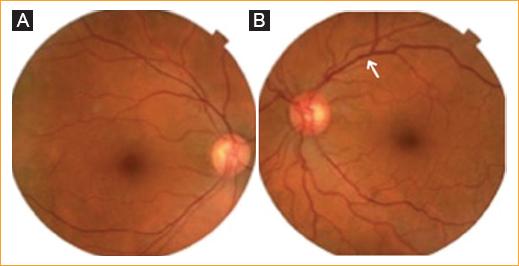

Mujer de 64 años que acude a la consulta porque «Tengo salido el ojo izquierdo y veo doble». Inicia hace 7 meses con sensación súbita de masa y presión en el ojo izquierdo, ardor, dolor, diplopía y edema bipalpebral. Niega antecedentes de trauma. Fue tratada en múltiples ocasiones con esteroides, sin mejoría. En la revisión por sistemas refiere cefalea crónica. Al examen oftalmológico se encuentra una agudeza visual normal bilateral, anisocoria y defecto pupilar aferente en el ojo izquierdo. En el test de saturación al rojo se observa desaturación al rojo del 40% en el lado izquierdo. Motilidad ocular de ojo izquierdo con hipofunción del recto lateral de –4 (Fig. 1). Proptosis leve en el ojo izquierdo a la exoftalmometría. La biomicroscopía del ojo izquierdo muestra una marcada ingurgitación vascular nasal y temporal. La presión intraocular y la refracción son normales en ambos ojos. Al fondo de ojo se observan vasos tortuosos en la arcada temporal superior izquierda (Fig. 2).

Figura 2 Fondo de ojo. A: ojo derecho normal. B: ojo izquierdo con tortuosidad en las arcadas temporales, principalmente superior (flecha).